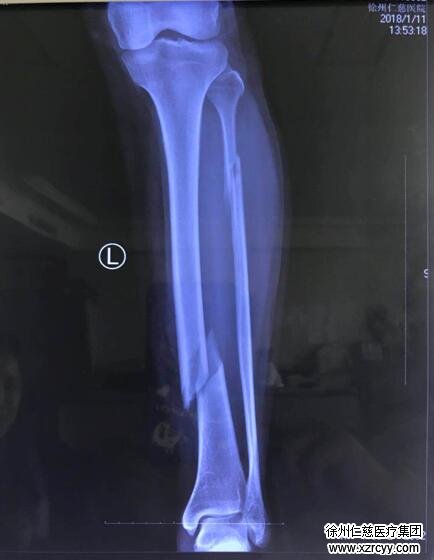

原来几天前,家住安徽萧县的曹女士下楼时踩到积雪不慎滑倒,在当地医院摄片显示骨折,为求进一步诊治,家人驾车将其送至betway在线登陆。betway在线登陆骨科邱东新接诊后,发现曹女士小腿下段完全错位,必须进行手术治疗,术前检查结果出来后,却让曹女士一家人傻了眼。“患者的化验报告上血色素值低,表示患者贫血,我们术前要帮患者纠正一下贫血状态,术中也要留存一些血备用,可是患者属于比较罕见的‘熊猫血’,血库中Rh-AB阴性血库存不足,所以患者暂时不能进行手术,风险太大了。”邱东新说。